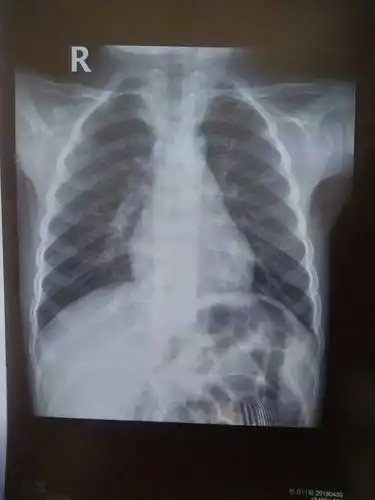

新生儿30天得肺炎,现在在妇幼icu,这是胸片,很严重吗